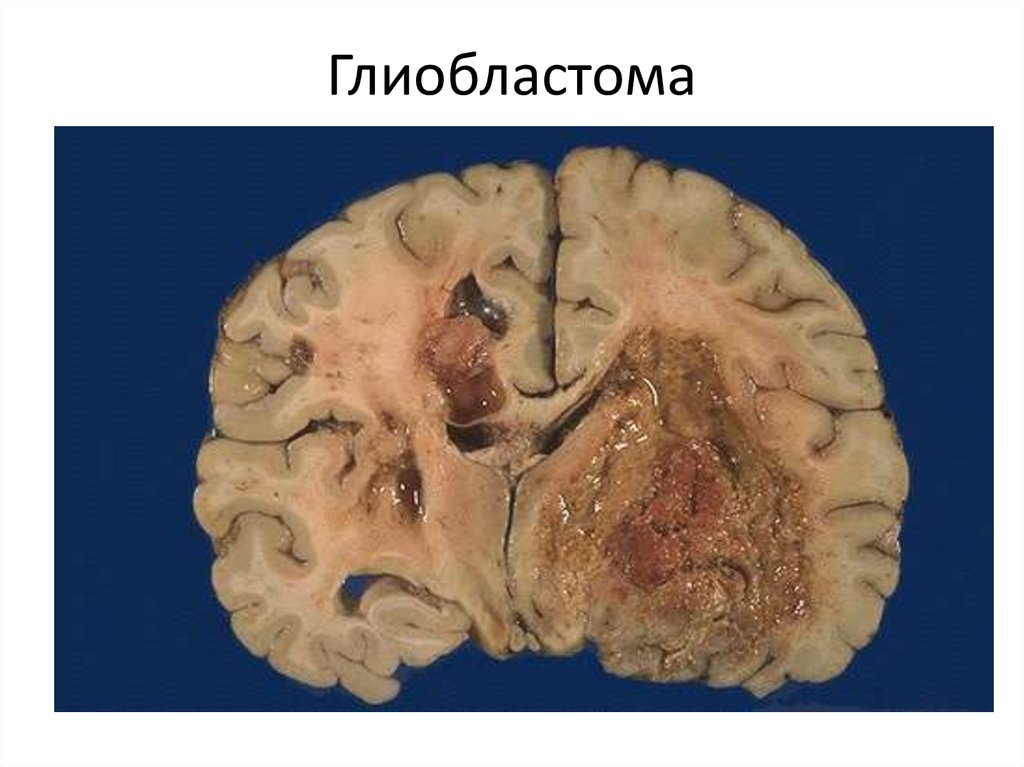

Глиобластома